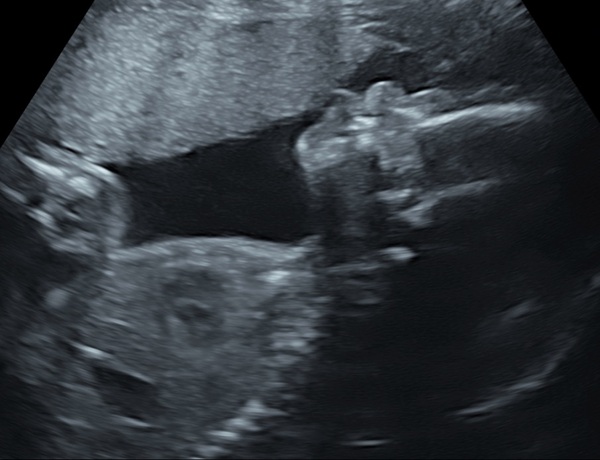

Growth scan today at 30+5! All measurements average size.

Aww @Rachael321 that's a brilliant profile photo! Glad to here little one is cooking nicely x

@Rachael321 wow what a dramatic experience and lovely scan picture.

So excited for everyone updating their weeks - we've come so far! @Treaclepie19 and @Rachael321 gorgeous scan pictures!!! 💕💕

@Rachael321 and @Treaclepie19 congratulations on your beautiful scans! They look so very babylike now it's amazing!